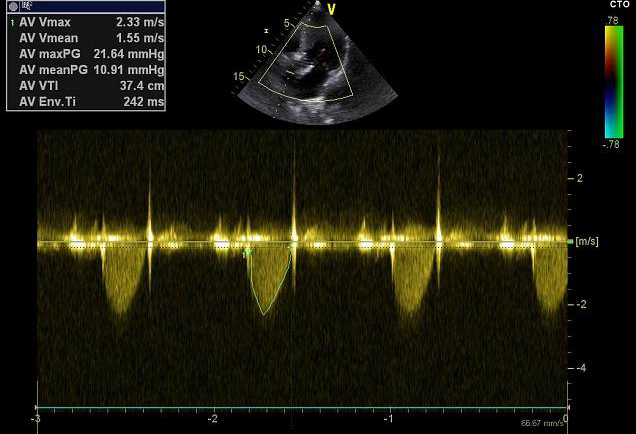

术后评估

球囊后扩后瓣膜形态良好

术前导管测量压差120mmHg;术后导管测量压差8mmHg